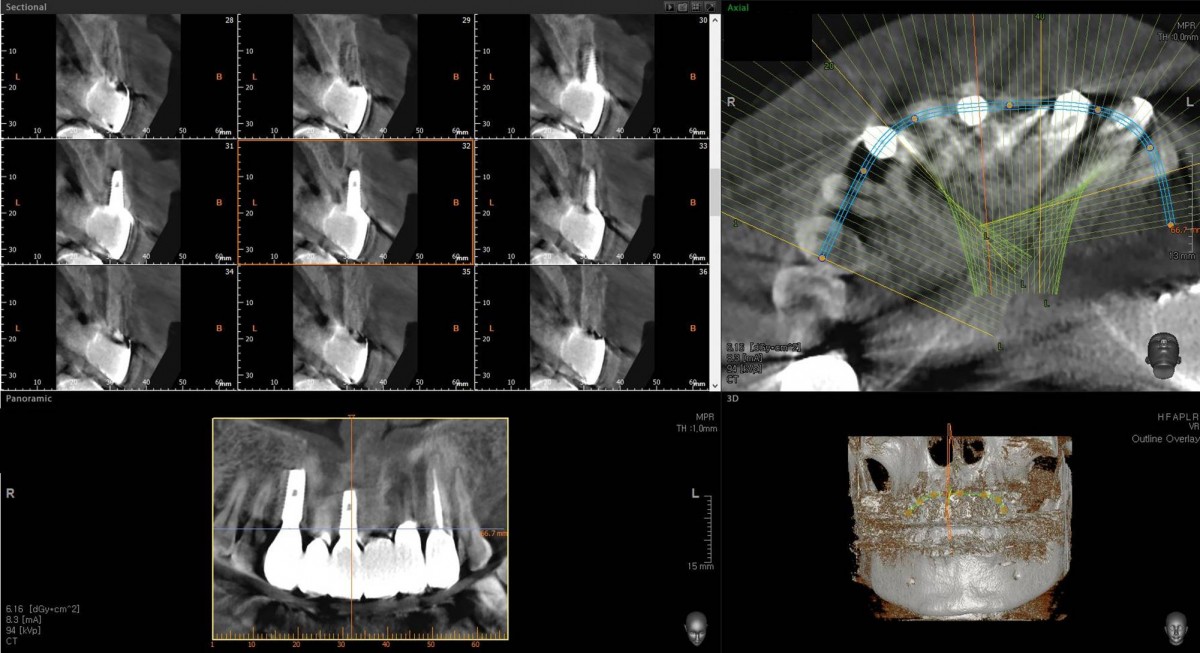

In the anterior maxilla, implant-supported fixed partial denture.

<GCpbc> A 58-year-old male is a patient undergoing implant installation in various parts. The old Br of the anterior maxilla has fallen

off and it is no longer possible to maintain it even temporarily, so a

treatment plan for the anterior teeth was made.